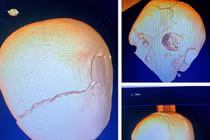

Nam sinh lớp 10 đang đi bộ về nhà thì bị nhóm thanh thiếu niên mang gậy tấn công dã man, gục tại chỗ. Nạn nhân bị nứt sọ, tụ máu bầm, hiện đang được cấp cứu.

Bệnh nhân nhập viện trong tình trạng nguy kịch, ổ dập não, tụ máu dưới màng cứng và vỡ xương sọ... Sau 5 ngày phẫu thuật, hồi sức tích cực... bệnh nhân đã hồi phục thần kỳ.